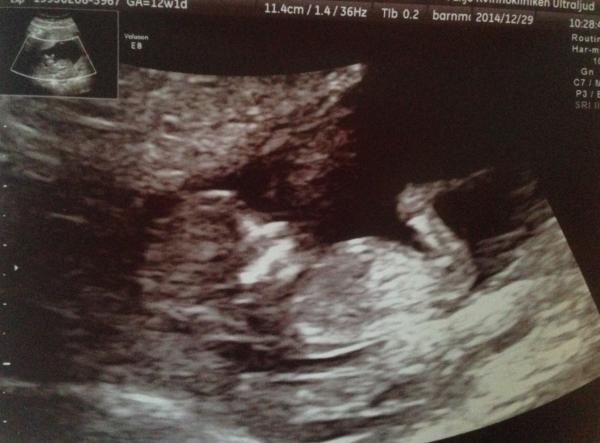

Jag är lite osäker på bf då jag haft tidigt mf och förmodligen blivit gravid igen ska få komma på vul om någon vecka och tidsbestämma graviditeten men räknar jag mf som sista mens så är jag på bim-3 idag bild på mitt test här under:) (bf 5/7.)